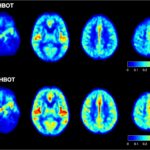

Brain Scans – no annotations (1)